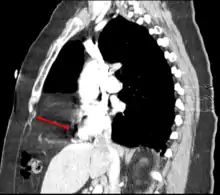

Morgagni hernia seen on a chest radiograph. | |

Morgagni hernia

This rare anterior defect of the diaphragm is variably referred to as a Morgagni, retrosternal, or parasternal hernia. Accounting for approximately 2% of all CDH cases, it is characterized by herniation through the foramina of Morgagni which are located immediately adjacent and posterior to the xiphoid process of the sternum.[4]